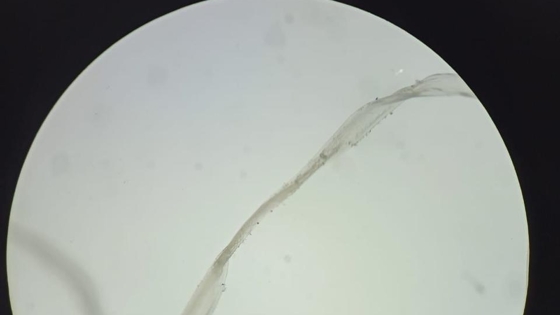

О случившемся рассказали представители министерства здравоохранения Кузбасса. Как оказалось, врачи-офтальмологи Кузбасской областной клинической больницы имени С.В.Беляева извлекли из глаза пациентки живого гельминта длиной четыре сантиметра.

– После осмотра врачи определили причину необычного образования – это дирофилярия. Заражение чаще всего происходит после укуса переносчиков личинок – комаров, слепней и клещей, – объяснили в ведомстве.

Отмечается, что в организме человека паразит растет, может мигрировать под кожей, но обычно не размножается, поскольку с укусом комара попадает только одна особь.

Пациентке выполнили операцию по удалению дирофилярии. Зрение женщины не пострадало.